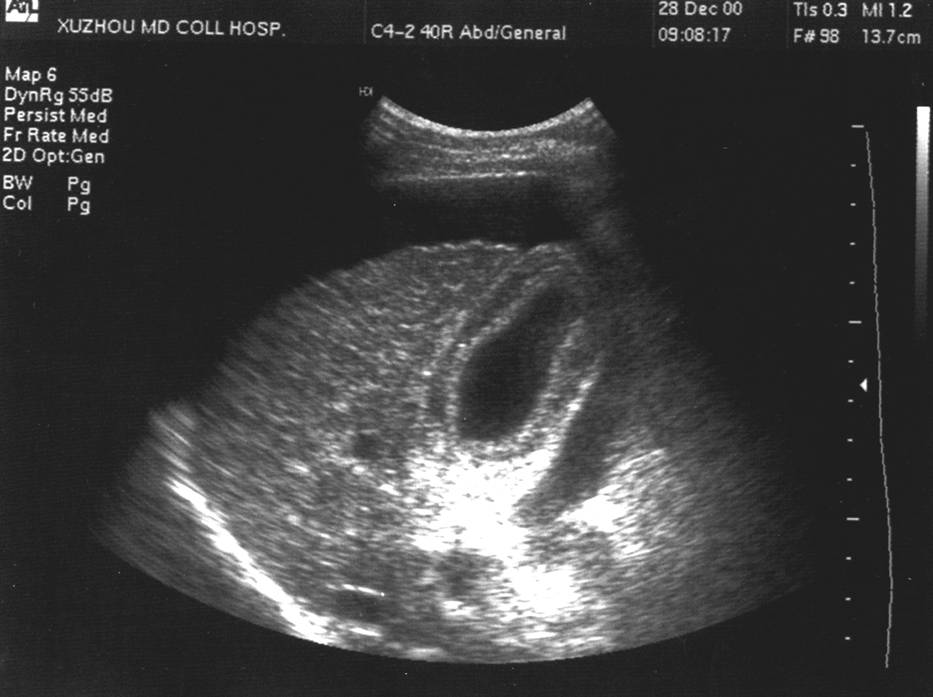

6、腹水

7、胆囊缩小,壁增厚,胆囊壁水肿严重者呈夹层

脾大、腹水

胆囊壁水肿